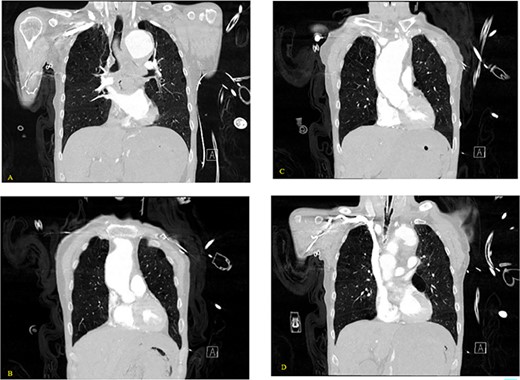

(A, B) Axial nonenhanced CT chest with contrast and (C) axial enhanced CT chest with contrast reveal an extensive clot around the aorta and around the esophagus with some mass effect on the pulmonary arteries and the LA. Clot fills the aorta.